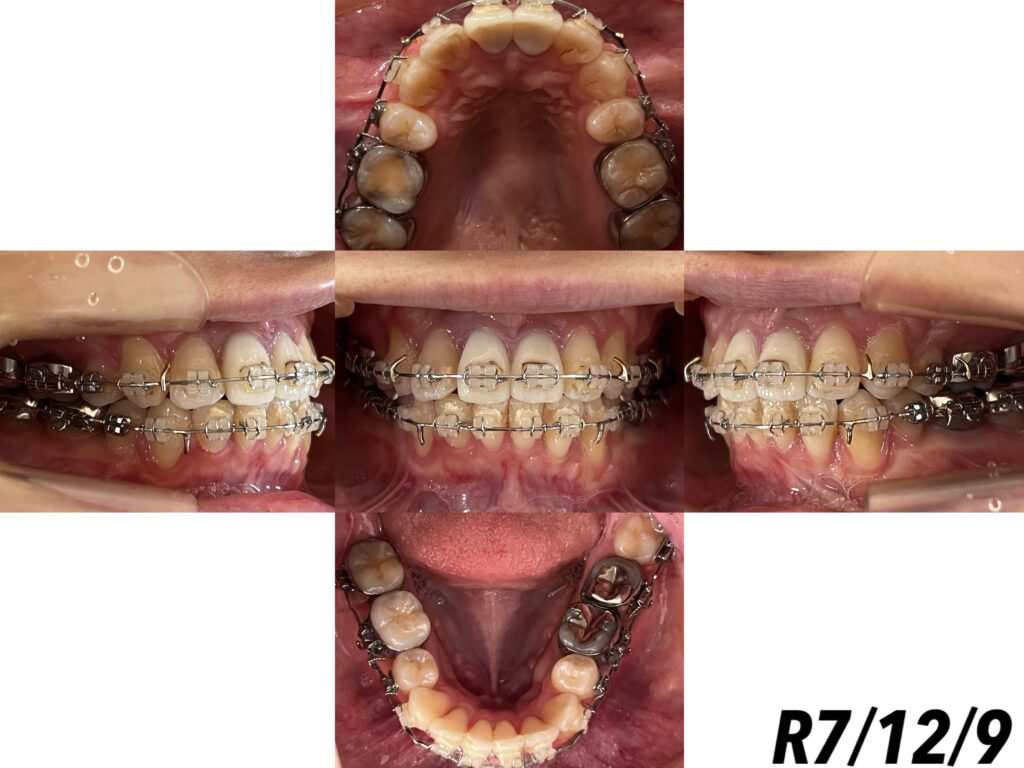

さて、年明け前になりますが、45回目の調整をしました🙏🏻🌈

今回は、上下顎とも、ワイヤーを外して、調整をしました🦷

上顎は細かい微調整と、下顎は上顎との臼歯部の幅が合っていなかった為、左下第三大臼歯にクラウンリンガルトルク(歯冠を内側に倒す力)を強く入れました👍🏻🤍

右下は第一大臼歯の捻れが取り切れていないので、捻転を取るように調整をしました︎👍🏻🤍

左下第二大臼歯と第三大臼歯のステップは、最初と比べると改善されたのが分かります🥹

顎間ゴムですが、左側だけⅢ級ゴムを使ってましたが、今回から右側も同じようにⅢ級を使うことになりました❣️